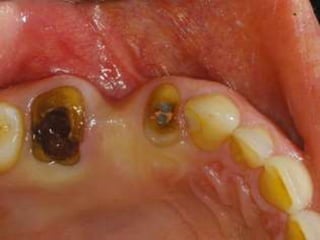

Contra-Indications

2. Non-Restorable tooth